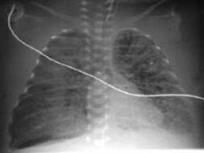

Рентгенологические признаки РДС.

В литературе нет указаний на наличие специфических признаков РДС, но наиболее типичными считаются:

Умеренное снижение пневматизации легких, различимы воздушные бронхограммы, границы сердца чёткие (Рис.4).

Рисунок 4

Рентгенограмма грудной клетки в прямой проекции в горизонтальном положении. (

Диагностика и лечение РДС недоношенных // метод. Рекомендация, 2007)